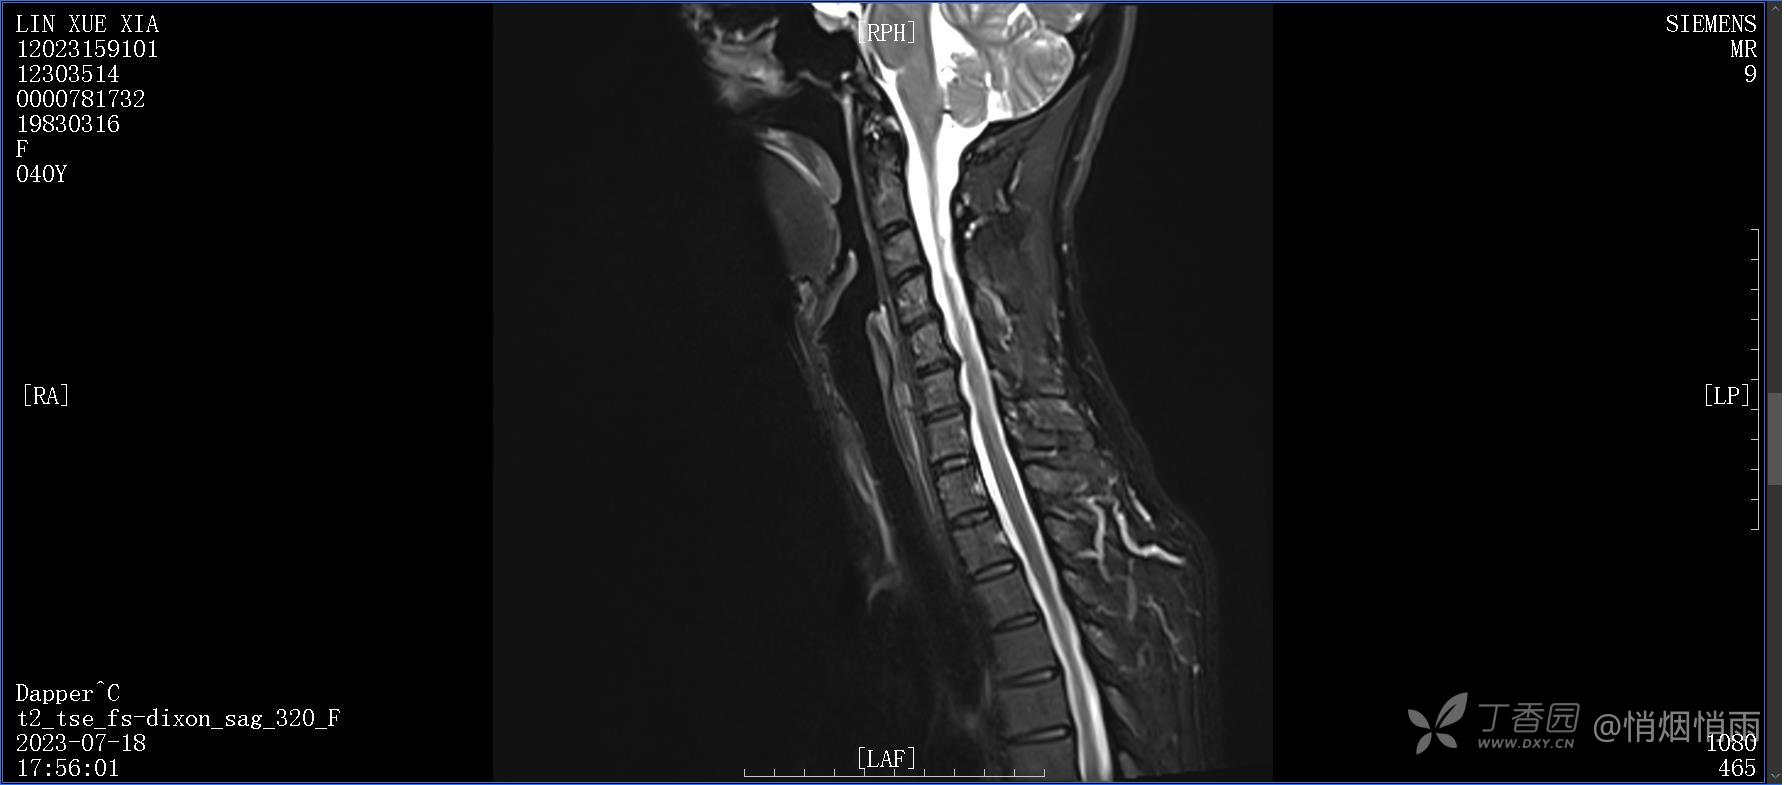

NeurothinkerZ 推荐患者女性,40岁,因右肩背部疼痛班活动受限4日余入院(2023-07-17)。

此患者行仰头抬下颌、低头收下颌以及将头转向患侧时疼痛明显,俯卧位时疼痛明显,仰卧状态起身时亦可感到疼痛,痛时剧烈。

目前的诊断,暂时依据辅助检查诊为肩袖损伤,但是患者疼痛的性质和特点,却不是单纯的肩袖损伤所致。考虑过胸廓出口综合征,但是该疾病会出现肩胛区的疼痛吗?(由于考虑到费用的问题,没再进行下一步的检查)带状疱疹会有如此的症状吗?

目前已予应用酮咯酸氨丁三醇,仅仅起效2小时左右,疼痛即开始发作,而且由于其用药后胃部疼痛,予更换为帕瑞昔布,效果同酮咯酸氨丁三醇。